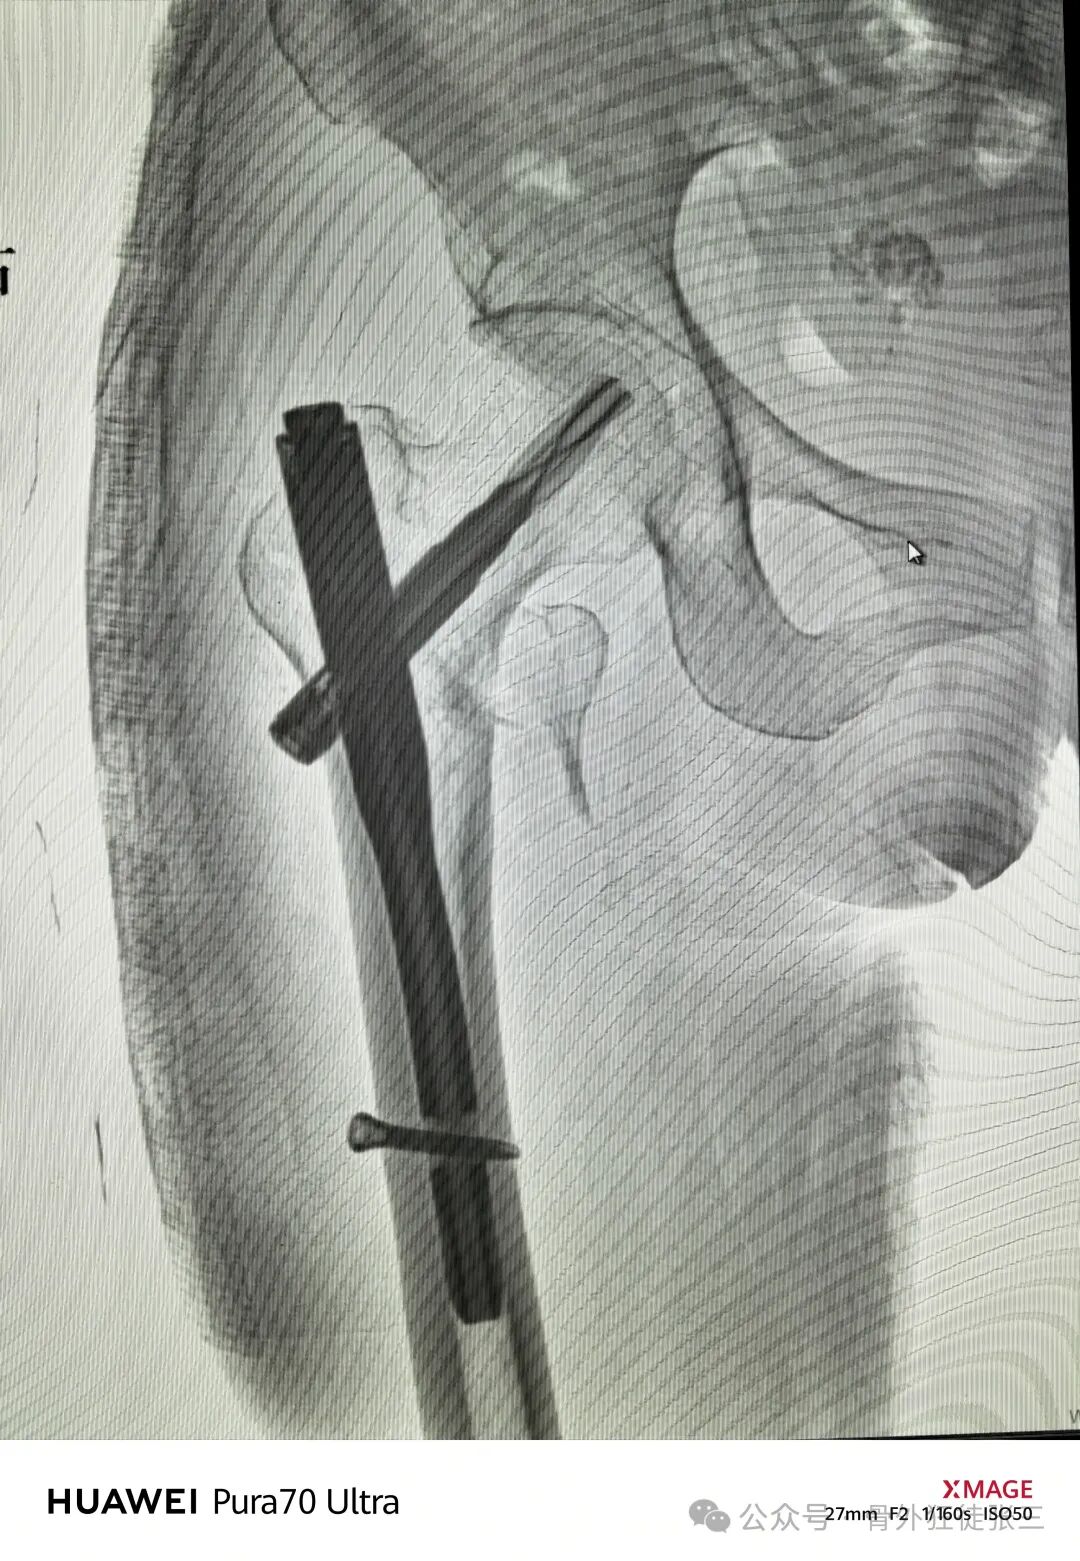

远端静态锁定

术中出血约50ml

手术从切皮到缝合

40分钟结束

透视18次

术后正位

进针点都是碎的

内移失败

瑕疵

内侧有个皮质骨块

内移动进针点说不定主钉插入时就可复位了